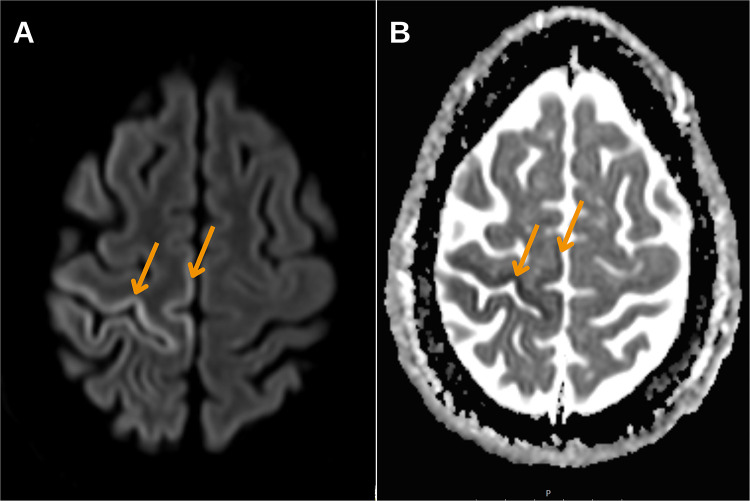

Case presentation: We present a rare case of cerebral infarction as a complication of retrograde cerebral venous air embolism following haemodialysis catheter removal in a young patient, with management leading to a favourable outcome. The diagnosis was confirmed based on clinical manifestations and neuroimaging findings, with air emboli identified in the subarachnoid space on the CT scan, followed by characteristic MRI changes defined for cerebral air embolism infarcts. Timely diagnosis allowed for the rapid initiation of hyperbaric oxygen therapy and the rehabilitation process, resulting in positive outcomes.

Conclusion: Timely neuroimaging-particularly CT within the first 2 hours-is critical for diagnosing CAEI. MRI findings, including cytotoxic and vasogenic oedema in a distal vascular distribution and leptomeningeal enhancement, further support diagnosis. Early identification and treatment initiation are essential for improving patient outcomes.